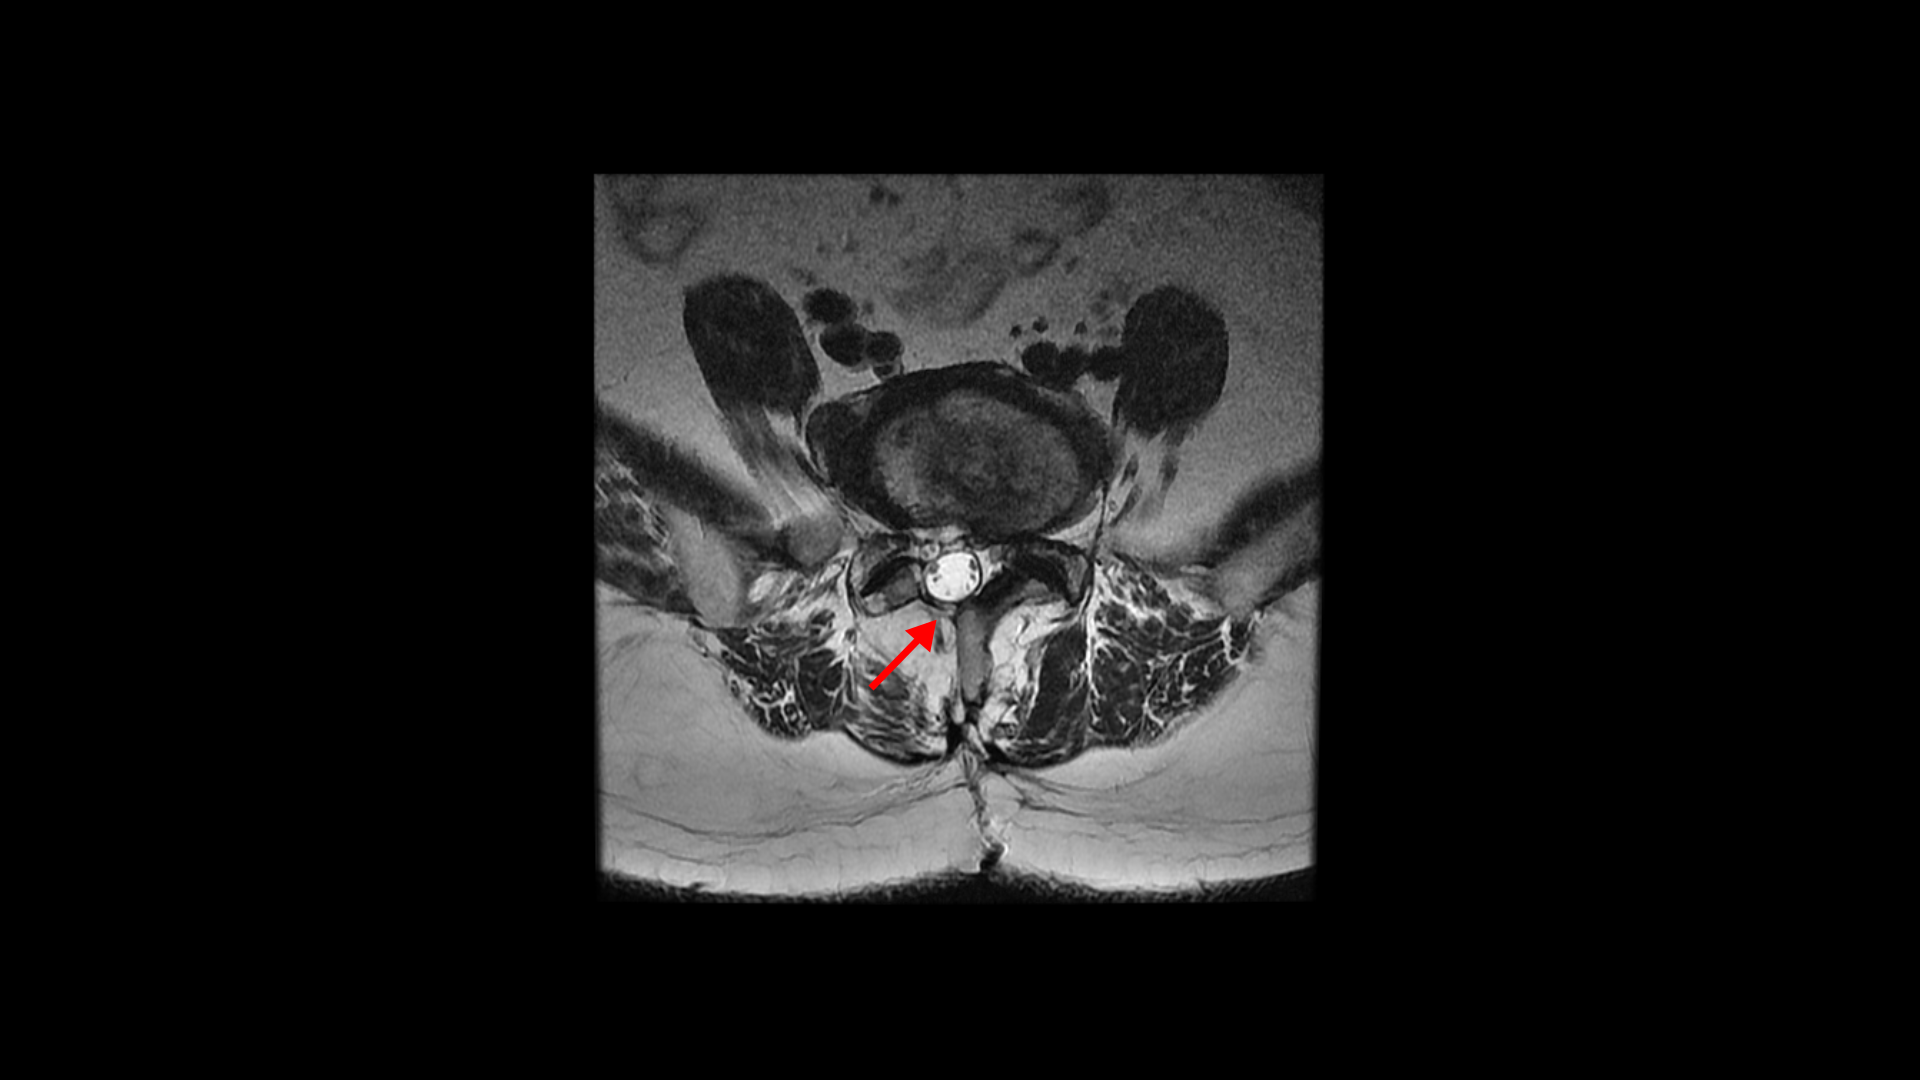

이 환자분은 허리수술을 여러 번 한 상태에서 결국에는 척추유합술까지 하셨습니다. MRI를 보시면 5번 1번 후궁에 수술한 자국이 보입니다.

4번 5번 후궁 양쪽으로 수술한 자국이 보입니다.

그런데 척추유합술을 하고 난 후 오른쪽 다리의 증상은 호전되었으나 상대적으로 증상이 괜찮았던 왼쪽 다리에 심한 방사통과 마비 증상을 호소하셨습니다. 수술한 병원의 집도의로부터 수술은 잘 됐으나 수술한 자리가 부어있기 때문에 신경을 눌러서 그런 거라고 1년 이상 기다리면 회복될 것이라는 얘기를 들으셨다고 합니다.